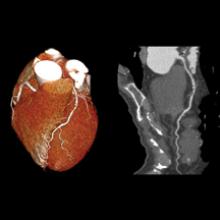

There has been growing clinical evidence to show computed tomography (CT) coronary artery calcium scoring shows a close correlation with a person’s long-term risk for heart disease. This data convinced the American College of Cardiology (ACC) to include CT calcium scoring in its revised guidelines for prevention and cholesterol released last fall. In addition, the ACC highlighted the evidence for CT calcium scoring as a late breaking session at its 63rd Annual Scientific Session in March.